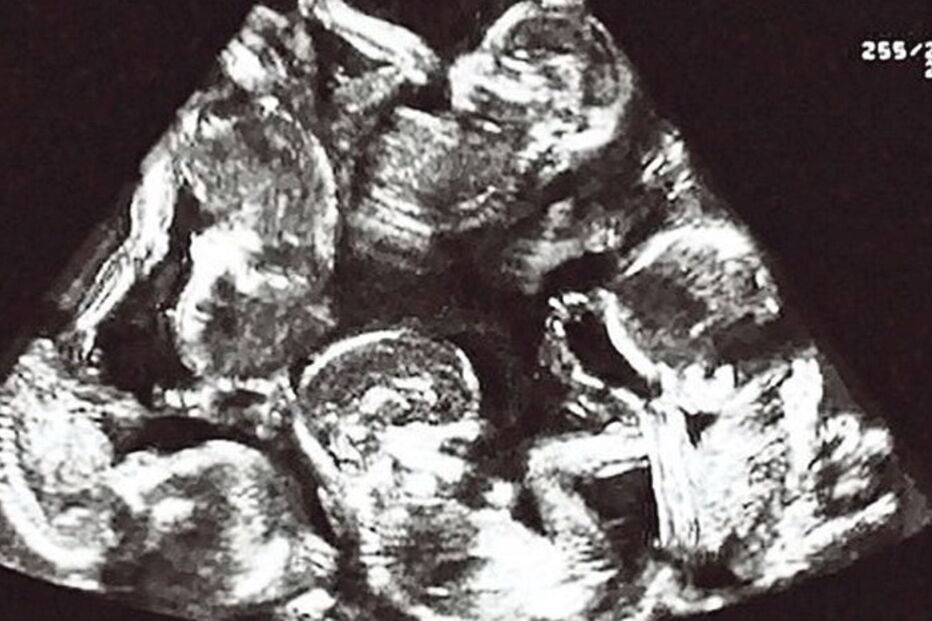

O casal já tinha uma criança e a ideia de aumentar a família sempre tinha estado nos planos de ambos. Após a primeira ecografia, foi dito a Alexandra que esperava gémeos: a alegria foi duplicada.

Apesar desta boa notícia o médico não ficou totalmente convencido. Pediu para o exame ser repetido e neste descobriu-se que, afinal, eram três as crianças que iriam nascer.

Era de esperar que as surpresas ficassem por aqui mas... ainda não. Um novo exame mostrou que Alexandra e Antonin iam ver a sua família crescer mais do que o previsto. Eram cinco os bebés que estavam a caminho.

De acordo com os médicos, a hipótese de uma mulher ficar grávida de cinco bebés de forma natural e sem recorrer a tratamentos é de uma em milhões, conta o jornal Aire Digital.

O parto foi assistido por 40 clínicos, entre médicos, enfermeiros e parteiras. Este foi um dia que entrou na história da República Checa, uma vez que não havia registo de quíntuplos a nascer no país.

Nasceram quatro meninos e uma menina: Alex, Daniel, Martin, Michael y Terezka.